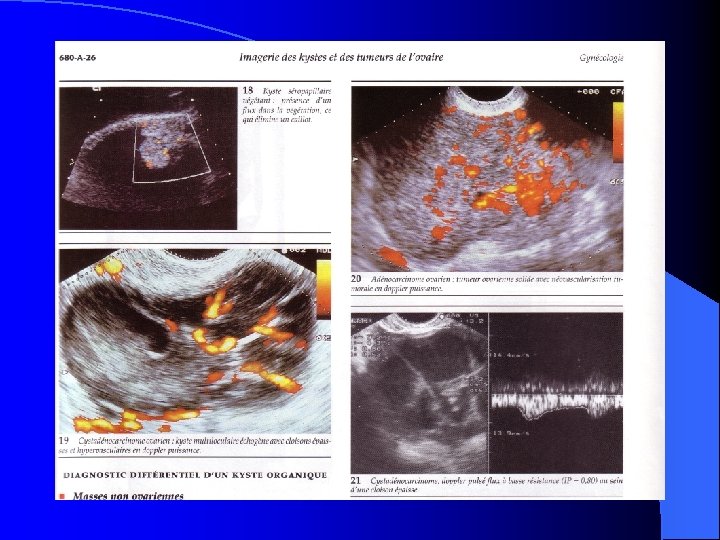

DIAGNOSTIC (SUITE) l EX. l complémentaires: Échographie : sonde externe et EEV = aspect échogène des T. solides et anéchogéne des kystes avec parfois structures mixtes: – Certains caractères en faveur de la bénignité : liquidien, uniloculaire à paroi fine – Nombreux intermédiaires : K. dermoide, mucineux ou endométriosiques. – En faveur de la malignité : hétérogénéité, contours irréguliers, cloisons épaisses et végétations – MAIS: la certitude diagnostique = examen histologique